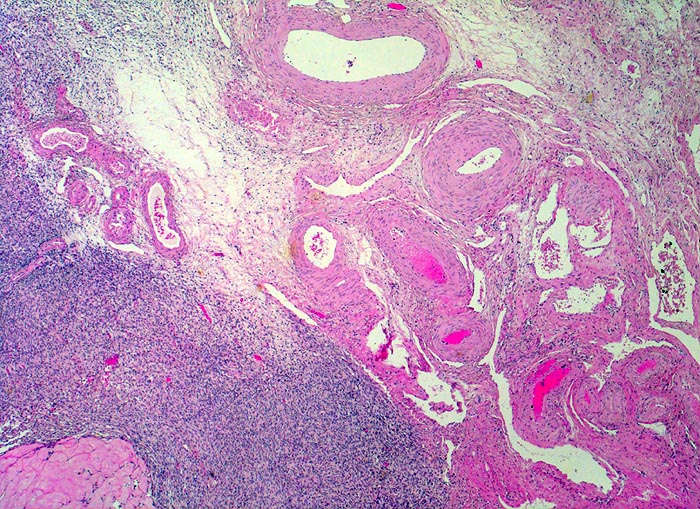

PathoPic ID 4284 - normales Ovar: Hilus

normales Ovar: Hilus

Ovar

Genitalorgane, weiblich

Rechts oben im Bild zahlreiche dickwandige Gefässe des Ovarhilus in lockerem Stroma eingebettet. Links unten im Bild Anschnitt eines Corpus albicans.

Histologie

25

72